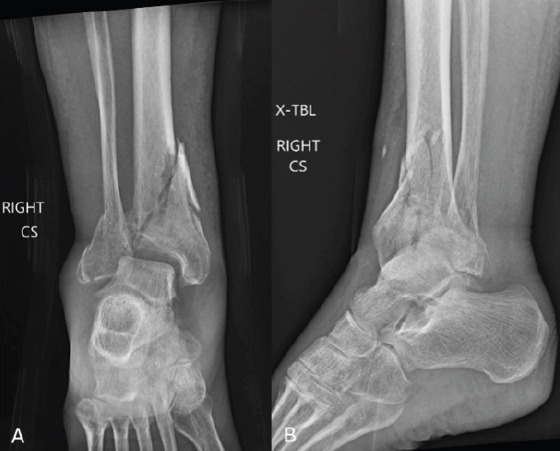

Case report: A 64-year-old female with a history of chronic obstructive pulmonary disease, hypertension, and a significant smoking history presented with a right tibial pilon and distal fibula fracture following a fall down the stairs. Due to her medical comorbidities and poor soft tissue envelope, she was at high risk for complications with ORIF. After discussing multiple treatment options, she elected to proceed with a tibiotalar intramedullary nail to optimize function while minimizing surgical morbidity. The procedure was performed using a suprapatellar approach, and an 8mm nail was inserted to preserve bone stock and future surgical options. Postoperatively, she progressed well, achieving full fracture healing by 9 months with minimal pain and functional independence. She declined further surgical intervention for hardware removal or ankle fusion, reporting satisfaction with her outcome.